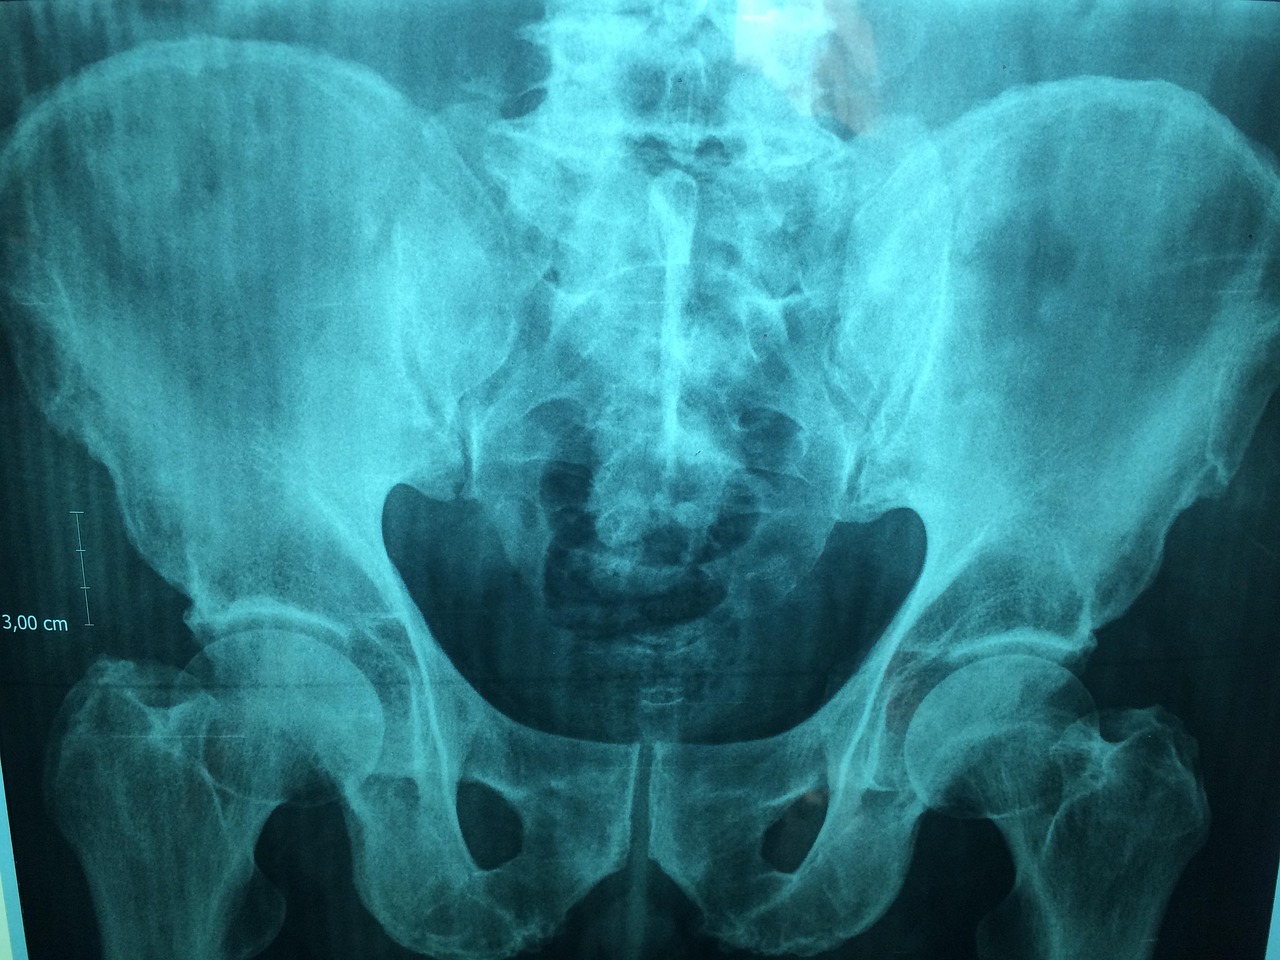

W zależności od wskazań klinicznych, zdjęcia wykonywane są w różnych projekcjach – najczęściej stosuje się projekcję AP (przednio-tylną), osiową, a także tzw. projekcję Y lub transtorakalną (boczną przez klatkę piersiową). Pozwala to na precyzyjną ocenę takich struktur jak kość ramienna, łopatka, obojczyk oraz stawy: barkowy, barkowo-obojczykowy i obojczykowo-mostkowy. Nowoczesne pracownie radiologiczne oferują cyfrowe przesyłanie wyników – obrazy trafiają bezpośrednio do systemu opisowego lekarza radiologa, a pacjent otrzymuje je zazwyczaj na nośniku elektronicznym (CD lub DVD). Takie rozwiązanie umożliwia szybkie przekazanie wyników zarówno do lekarza prowadzącego, jak i do innych specjalistów w razie potrzeby dalszej diagnostyki lub konsultacji.

Interpretacja wyniku prześwietlenia barku opiera się na analizie charakterystycznych zmian widocznych w strukturach kostno-stawowych. W opisach radiologicznych często pojawiają się określenia takie jak zmiany zwyrodnieniowe, które mogą być opisane jako początkowe, stopniowe lub zaawansowane. Oznaczają one procesy degeneracyjne prowadzące do utraty chrząstki stawowej i powstawania osteofitów, co przekłada się na ból oraz ograniczenie ruchomości. Innym często spotykanym pojęciem jest PHS (periarthritis humeroscapularis), czyli zespół bolesnego barku – termin ten obejmuje grupę objawów związanych z zapaleniem, uszkodzeniem ścięgien lub kaletek okołostawowych, a także zmianami w obrębie stawu barkowo-obojczykowego.

Wynik badania RTG może również zawierać informacje o cechach zapalenia stawu, takich jak obrzęk tkanek miękkich czy zwężenie szpary stawowej, a także o obecności uszkodzeń ścięgien lub innych struktur miękkotkankowych. Radiolog ocenia także stan stawu barkowo-obojczykowego – jego deformacje, zwapnienia czy ślady przebytych urazów mogą mieć istotne znaczenie dla dalszego postępowania terapeutycznego. W zależności od wykrytych nieprawidłowości lekarz prowadzący może zdecydować o konieczności rozszerzenia diagnostyki (np. o rezonans magnetyczny) lub wdrożeniu odpowiedniego leczenia zachowawczego bądź operacyjnego.

• Zwężenie szpary stawowej na zdjęciu RTG może sugerować rozwijającą się chorobę zwyrodnieniową lub przewlekłe przeciążenia.

• Zwapnienia w obrębie tkanek miękkich są typowe dla przewlekłych stanów zapalnych i mogą wskazywać na tzw. wapniejące zapalenie ścięgien.

• Nierówność powierzchni kostnych oraz obecność osteofitów to objawy postępujących zmian degeneracyjnych.

• Złamania i przemieszczenia kości są jednoznacznym wskazaniem do pilnej interwencji ortopedycznej.

• Zmiany destrukcyjne lub ubytki kostne mogą być sygnałem poważniejszych schorzeń, takich jak martwica kości czy proces nowotworowy.